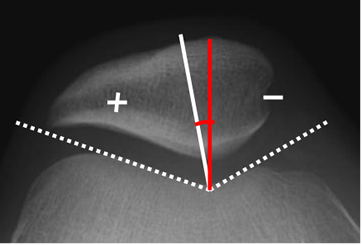

Numerosos métodos han sido propuestos, para la adquisión de radiografías axiales de la articulación patelofemoral. La mas utilizada es la proyección de Merchant, con flexión de 30º y rotación lateral de la pierna. (8). Con ella se mide el ángulo de congruencia y el ángulo de inclinación patelar.

Fig 6. Angulo de congruencia.

Rx tangencial a 30º. Bisectriz del ángulo del surco (Línea blanca) y línea que une el centro del surco, con la parte inferior de la patela. (Línea roja).

Fig 7. Angulo patelofemoral.

Rx tangencial a 30º. Angulo normal, de vértice medial.